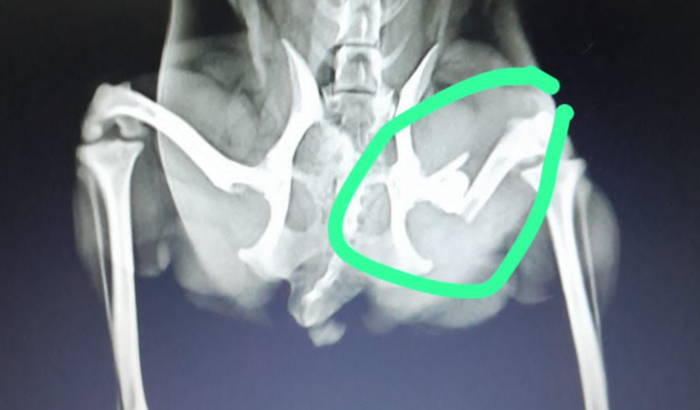

No último dia 27, Lua sofreu um acidente terrível: caiu de uma escada e fraturou a perna. Desde então, ela está sentindo muita dor e precisa de nossa ajuda para se recuperar.

Levei Lua ao veterinário e a cirurgia é a única opção para que ela possa voltar a correr e brincar como antes. O problema é que a cirurgia custa R$ 3.500,00 e, infelizmente, não tenho condições de pagar esse valor.